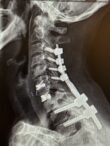

Benjamin R. Cohen, M.D., F.A.A.N.S., F.A.C.S. is a board certified neurosurgeon specializing in spinal surgery. His practice includes revision spine surgery, adult scoliosis, and the treatment of spinal tumors and infection.

For more complex cases, including treatment for adult scoliosis and spinal deformities, Dr. Cohen partners with Marc Agulnick, M.D., a fellowship-trained orthopedic spine surgeon, and Thomas Davenport, M.D., a fellowship-trained plastic surgeon. Although each doctor is a partner in their own practice, Dr. Cohen has learned that this team approach optimizes patient care and produces better surgical outcomes.